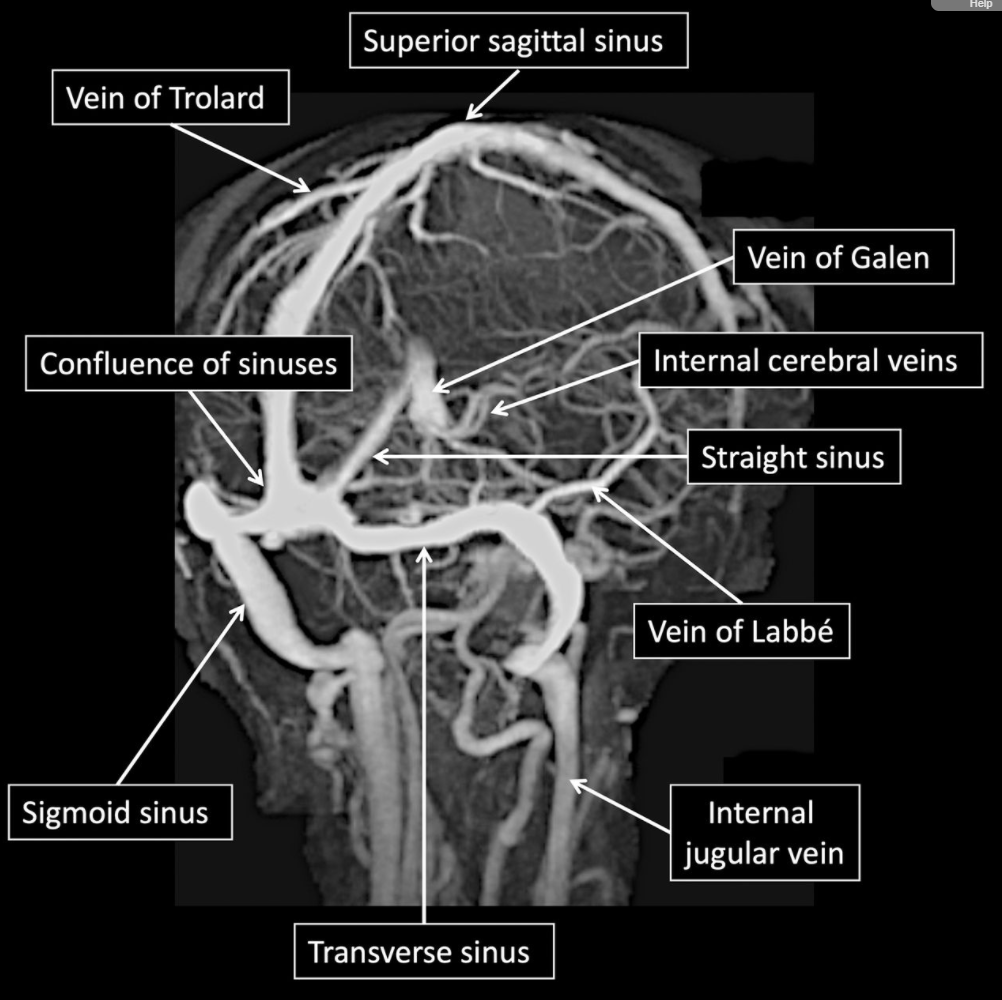

• Cerebral Veins 🧠